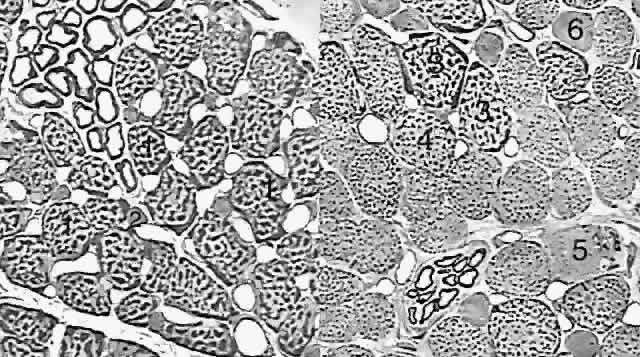

Fig. 3. Thin section (1-μm) light micrographs of the fiber types in human medial rectus muscle. (Left) Orbital layer. Singly innervated fibers (SIFs, 1) are large and densely packed with dark-staining aggregates of mitochondria, especially in the periphery of each fiber. Multiply innervated fibers (MIFs, 2) are much smaller and contain fewer mitochondria. (Right) Global layer. The three types of SIFs really form a continuum distinguished by their density of mitochondria. The largest and most granular fiber (3) is very similar to the orbital SIF; the other two SIFs (4 and 5) have fewer mitochondria. Global MIFs (6) are still smaller, contain fewer mitochondria, and resemble orbital MIFs. (Courtesy of Dr. John D. Porter.)

The orbital layer of each EOM contains two distinct muscle fiber types (Fig. 3A).4 About 80% of fibers in the orbital layer of each EOM are fast, twitch-generating, singly innervated fibers (SIFs) resembling mammalian skeletal muscle fibers, whereas 20% are multiply innervated fibers (MIFs) that either do not conduct action potentials or do so only in their central portions.4 Orbital SIFs are relatively small in diameter, and their abundant mitochondria impart a dark staining characteristic with Masson's trichrome. The metabolism and blood supply of orbital SIFs are tailored to their unique mechanical loading and nearly continuous activity. Orbital SIFs are specialized for intense oxidative metabolism and fatigue resistance.4 The vascular supply in the orbital layer is high,2 about 50% greater in humans than the well-perfused global layer. Orbital SIFs express unique myosin isoforms, perhaps related to the requirements of fast twitch capability against continuous loading, because alterations in EOM activity patterns can change EOM-specific myosin heavy chain gene expression.7

The global layer contains one MIF and three designated types of SIFs that really form a continuum distinguished by their density of mitochondria (see Fig. 3B). The largest and most granular SIF is very similar to the orbital SIF, having almost as many mitochondria, whereas the other two SIFs have correspondingly fewer mitochondria. Global MIFs are still smaller, contain fewer mitochondria, and correspond to the orbital MIFs. No spindles are present in the global layer, but the anterior tendonous termination of the global layer of the rectus EOMs contains palisade endings. Palisade endings are distributed along the width of each rectus tendon near the insertion and presumably act as stretch receptors.